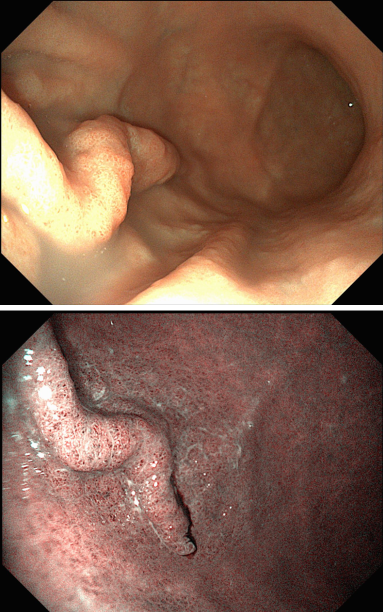

58세 여성 환자에서 위내시경 검사 중

위체하부 대만에서 비교적 드문 형태의 병변이 발견되었습니다.

** 아래는 본 증례의 실제 내시경 사진입니다.**

내시경 소견상 종양과 유사하게 보이는 경우가 많아

반지세포암종(signet ring cell carcinoma), MALT 림프종, 형질세포종 등과의 감별이 필요합니다.